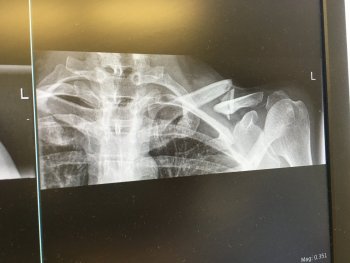

Broke my collarbone too:

IMG_0276.jpeg